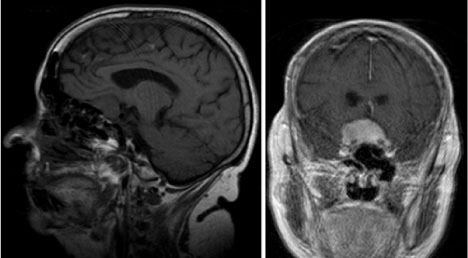

偶然发生的脑膜瘤,顾名思义,是在脑成像上诊断的,通常是脑部的磁共振图像,没有组织病理学证实。虽然影像学表现通常很有特点,但许多病变在影像学上可以模仿脑膜瘤的表现(图1和图2)。如果选择保守方法,这种可能性强调了初始密切随访评估的重要性。脑膜瘤的两个经典鉴别诊断是血管外皮细胞瘤和脑膜转移。血管外皮细胞瘤是一种少见的颅内恶性肿瘤,据信占全部原发性脑膜肿瘤的2%-3%。血管外皮细胞瘤较初被认为是脑膜瘤的一个亚组(血管母细胞变型),但自1993年以来,世卫组织将它们归类为一个独特的实体。血管外皮细胞瘤以其侵袭性、高复发率和潜在的转移而闻名。诊断时的中位生存期约为13年。

图1:冠状位T1加权磁共振成像增强显示轴外室管膜瘤,影像学上类似脑膜瘤。

这位患者是一位79岁的女性,主诉喉咙肿胀。体检时,她被发现左侧颈内动脉有杂音。作为评估的一部分,她接受了颈部磁共振血管造影,显示存在无症状的颈内动脉狭窄。脑部磁共振成像显示偶然发现的鞍结节脑膜瘤(图3)。患者没有视觉症状,检查时神经系统完好无损。她的内分泌检查也很正常。考虑到她的年龄和病变的大小,决定进行系列影像学随访。此后她接受了5年多的随访,没有肿瘤生长或视觉症状。